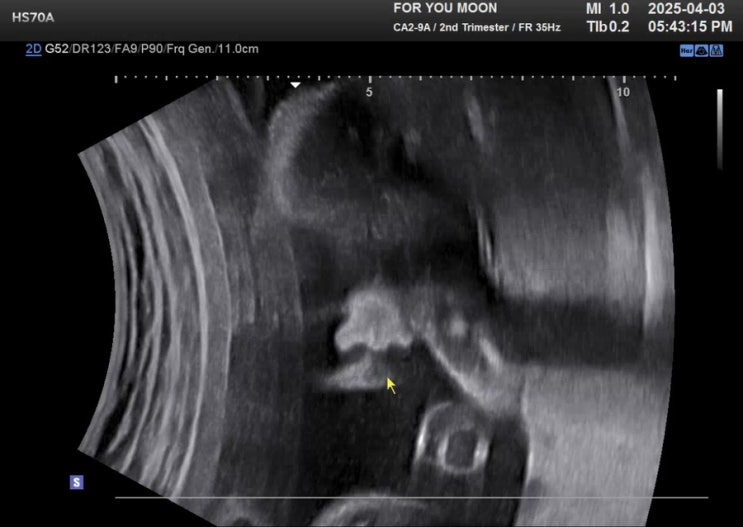

임신 23-25주차 기록_제주태교여행, 신기한 태동 경험, D-100진입!!

23, 24, 25주차 기록 그만 밀리고 빠르게 적어보자구~~~ 23주차 태동이 늘었다 는건가 아니면 가지가 커져...